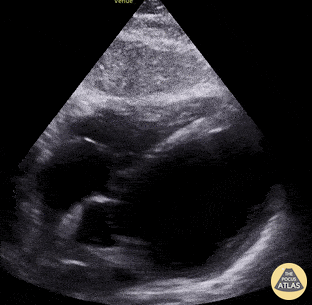

Apikaler Blick: Hochgradig eingeschränkte LV-Funktion (Quelle: thepocusatlas.com)

Subkostaler Blick: Hochgradig eingeschränkte LV-Funktion (Quelle: thepocusatlas.com)

Apikaler Blick: (Akute) RV-Belastung (Quelle: thepocusatlas.com)

Subkostaler Blick: Perikardtamponade (Quelle: thepocusatlas.com)